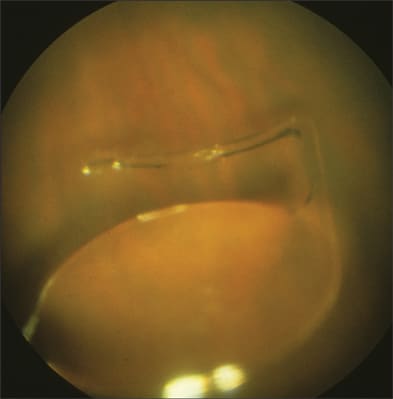

The majority of patients with posterior IOL dislocations are treated surgically, by either a limbal or a pars plana approach. If the IOL is still supported to some degree by the capsular remnants, an anterior-segment (limbal) approach may be considered (Figure 2). However, when the patient is supine on the operating table, the IOL frequently falls further posteriorly, making a limbal approach more difficult. Pars plana vitrectomy (PPV) techniques offer several advantages to a limbal approach, including more complete and controlled removal of formed vitreous, better access to the posterior vitreous cavity and better ability to address potential intraoperative complications, such as retinal tear, suprachoroidal hemorrhage or progressive IOL dislocation into the posterior vitreous (Figure 3).

Figure 3. Dislocated anterior-chamber intraocular lens on the retinal surface.